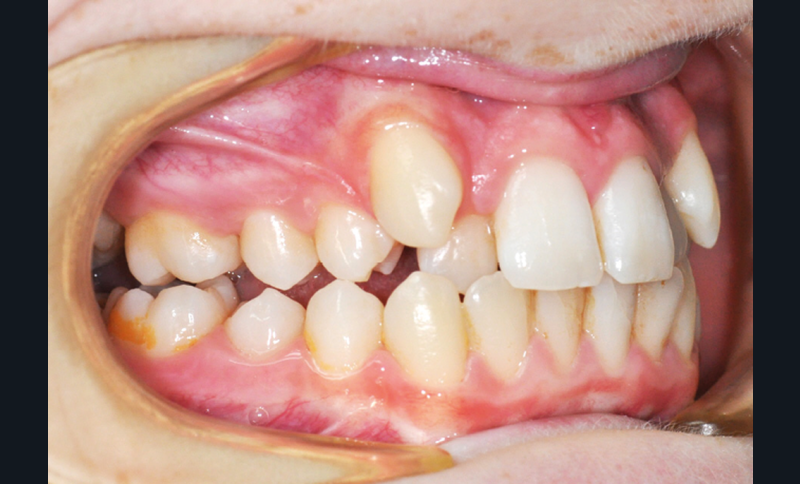

Julien nous consulte à l’âge de 11 ans et 4 mois pour des raisons essentiellement esthétiques, afin d’améliorer l’alignement de ses incisives maxillaires (fig. 1a-d) ; son chirurgien-dentiste l’a toutefois alerté sur un problème d’évolution des 35 et 47, dont l’inclusion a été mise en évidence lors d’un contrôle radiographique (fig. 1e).

L’examen intra-oral met en évidence une occlusion inversée bilatérale ainsi qu’un manque de place conséquent pour les incisives latérales maxillaires en palato-position et une infra-vestibulo-position de 13 et 23. Le patient est déjà en denture adulte jeune, hormis la persistance de la 75. L’occlusion est en classe II, plus marquée du côté droit sans engendrer de déviation des médianes incisives, d’où une mésio-position plus importante de la 13 par rapport à la 23.